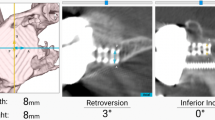

After registration, participating surgeons with knowledge of the preoperative plan were blinded to the navigation screen and attempted to implement their preoperative plan by simulating placement of a central-axis cage drill (Figs. 1 and 2). Two-hundred thirty screenshots of surgeons’ simulated guide pin placement were included (aTSA = 66, rTSA = 164). Displacement, error in version and inclination, and overall malposition from the preoperatively-planned target point were stratified by the Favard classification [12] describing superior-inferior glenoid wear: E0 (n = 89) = superior humeral migration with no glenoid erosion; E1 (n = 81) = concentric glenoid erosion; E2 (n = 29) = glenoid erosion predominantly in the superior pole; E3 (n = 29) = global glenoid erosion more severe in the superior pole; E4 (n = 2) = glenoid erosion predominantly in the inferior pole. All glenoids were classified according to the Favard classification [12] using preoperative CTs by a single fellowship-trained upper-extremity surgeon (R.C.S). Components were considered malpositioned for version/inclination errors > 10° or displacement from the starting point > 4 mm.

Example of a computer navigation screenshot showing surgeon-blinded simulated placement of the central-axis guide pin (yellow outline), attempting to match the preoperative plan (blue outline, 1° of retroversion and 3° of superior inclination); the values for the starting point location, version, and inclination for the simulation were then compared with the preoperatively planned component position to determine displacement, version and inclination error, and malposition. P, posterior; A, anterior; S, superior; I, inferior

Inclination error

Mean inclination error was 7.1 ± 5.6 (aTSA = 4.8 ± 4.8°, rTSA = 8.1 ± 5.7°). Mean inclination error did not differ based on Favard classification [12] overall (P = 0.764; E0 = 7.2 ± 5.6°, E1 = 6.6 ± 5.7°, E2 = 7.4 ± 5.6°, E3 = 8.2 ± 5.7°, E4 = 6.0 ± 5.7°) nor when stratified by aTSA versus rTSA. No differences in inclination error were found when grouped (Fig. 3B; P = 0.833). There was no difference in inclination error between glenoids without wear and glenoids with superior wear (7.2 ± 5.6 vs. 7.8 ± 5.6, P = 0.527) (Figs. 2 and 3).